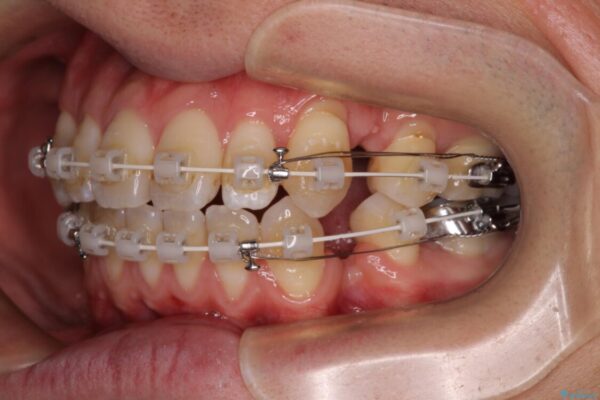

治療途中

• 口元の突出感を改善!目立ちにくいワイヤー矯正で自信を持てる自然な横顔に 治療途中画像

装置は、透明感のあるクリアブラケットとホワイトコーティングされたワイヤーを使用した、目立ちにくい審美装置を選択。

周囲に気づかれにくく、日常生活にも自然に溶け込みます。